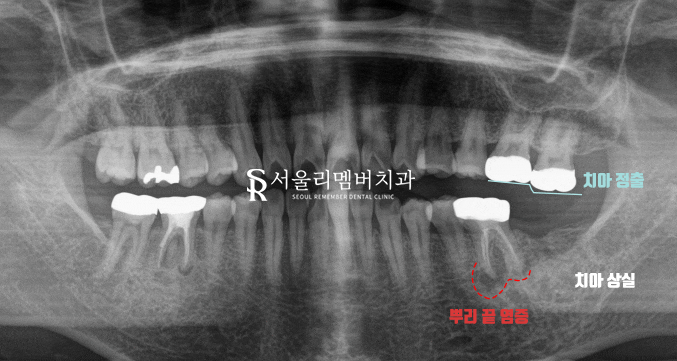

초진 파노라마 사진을 살펴보니

좌측 아래 어금니 하나가 빠져 있었습니다.

문제는 여기서 끝이 아니었는데요.

바로 옆에 있는 인접치는

이전에 신경치료를 받았던 곳에

병소가 또다시 재발하여

뿌리 끝에 염증이 잡혀 있었으며

맞물리는 대합치 상실로 인해